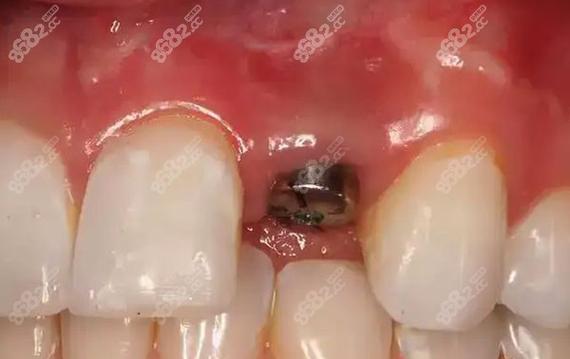

(图片来源网络,侵删)